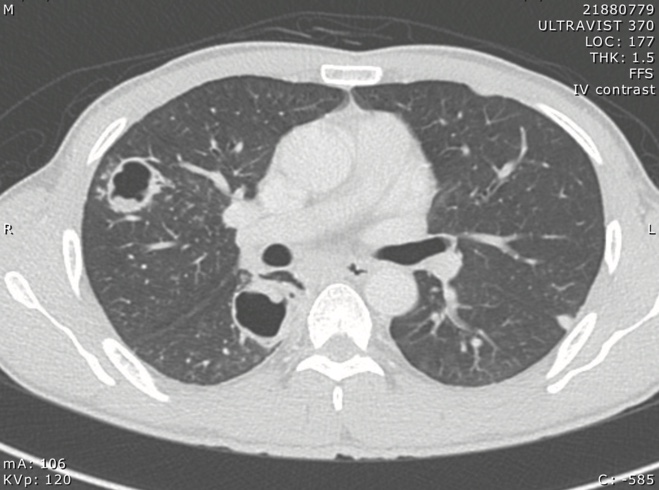

ภาพรังสีทรวงอก

อาศัยการซักประวัติการกินปูหรือกุ้งที่ปรุงไม่สุก การตรวจพบไข่พยาธิใบไม้ปอดในเสมหะ (sputum fresh smear) หรือในอุจจาระทำให้วินิจฉัยโรคได้ โดยจะมีโอกาสพบได้มากขึ้นถ้าทำการตรวจหลายครั้ง โดยไข่พยาธิจะมีสีน้ำตาลทองรูปยาวรีขนาดประมาณ 68-118 ไมครอน x 39-67 ไมครอน ใน Paragonimus heterotremus จะมีเปลือกหนาสม่ำเสมอตลอด ส่วน Paragonimus westermani เปลือกไข่ส่วนตรงข้ามกับฝา (operculum) จะหนากว่าส่วนอื่นๆ การตรวจอื่นๆ ได้แก่ การตรวจเลือดโดยใช้วิธี immunoblot assay โดยการใช้เอนติเจนจากตัวพยาธิ การทำ skin test เป็นต้น การตรวจ pleural fluid จะพบลักษณะของ exudate ที่มี eosinophil สูง การตรวจภาพรังสีทรวงอกจะพบ nodule, pneumothorax, interstitial opacities, cavity, ring cyst ลักษณะคล้าย bronchiectasis ได้8,9 ส่วน pleural effusion พบได้ประมาณร้อยละ 48 ถึง 624,10 ผู้ป่วยประมาณร้อยละ 10 ถึง 20 มีภาพรังสีทรวงอกปกติได้11 ภาพรังสีคอมพิวเตอร์พบ parenchymal consolidation ในผู้ป่วยส่วนใหญ่ linear streak พบได้ร้อยละ 3 ถึง 412 พบ ring shadow ได้ ประกอบด้วย cyst ที่มีพยาธิอยู่ติดกับผนังของ cyst7 และอาจพบ pleural nodule ได้